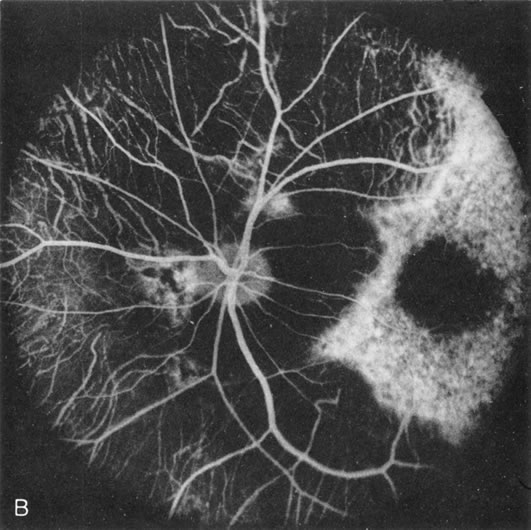

Dye leakage in RP may occur from the retinal vessels or at the level of the retinal pigment epithelium (Fig. 1B).2–4 The leakage may be seen in the macula and posterior pole, along the vascular arcades in the distribution of the radial peripapillary capillaries, and in the periphery (where an exudative vasculopathy resembling Coats' disease is suggested).